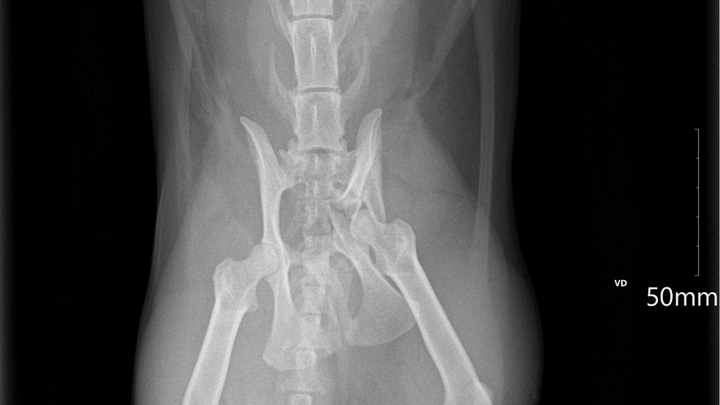

Recently, Kali chewed through the fence of her cat patio and escaped. When I found her, her leg was numb. At the vet, I learned she suffered a severe pelvic fracture—an injury that won’t heal on its own and requires surgery. Without it, she may never be able to move her right leg again.

Kali is having part of her pelvis removed, and it will be replaced with a flexible metal plate. It’s a major surgery — and, unfortunately, it comes with a major price tag.